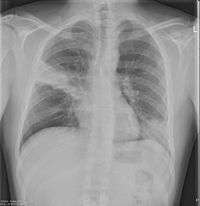

When signs are discovered, chest X-rays, examination of the blood and sputum for infectious microorganisms and blood tests are commonly used to diagnose CAP. Diagnostic tools depend on the severity of illness, local practices and concern about complications of the infection. All patients with CAP should have their blood oxygen monitored with pulse oximetry. In some cases, arterial blood gas analysis may be required to determine the amount of oxygen in the blood. A complete blood count (CBC) may reveal extra white blood cells, indicating infection.

Chest X-rays and X-ray computed tomography (CT) can reveal areas of opacity (seen as white), indicating consolidation. CAP does not always appear on x-rays, because the disease is in its initial stages or involves a part of the lung an x-ray does not see well. In some cases, chest CT can reveal pneumonia not seen on x-rays. X-rays can often mislead, as Heart failure or other types of lung damage can mimic CAP on x-rays.[12]

X-ray findings indicating hospitalization include:

- Involvement of more than one lobe of the lung

- Presence of a cavity

- Pleural effusion